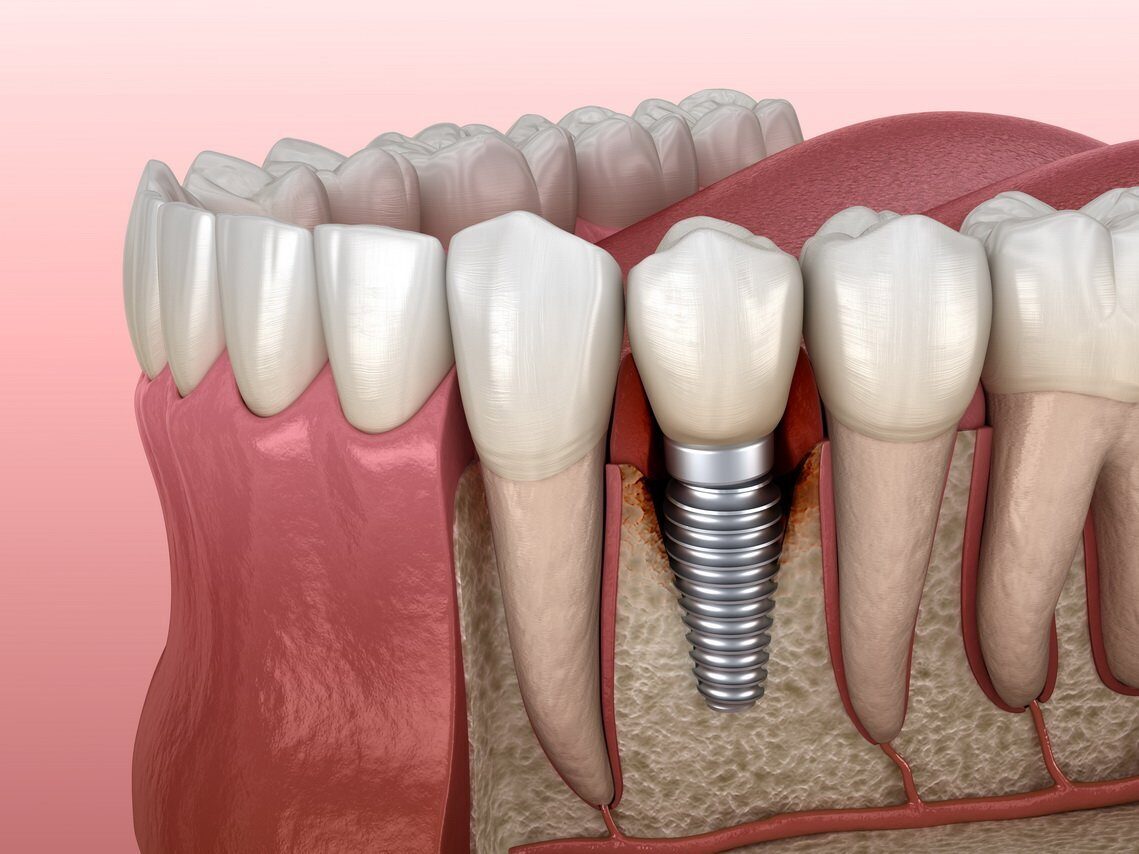

Современная стоматология: Железные зубные импланты